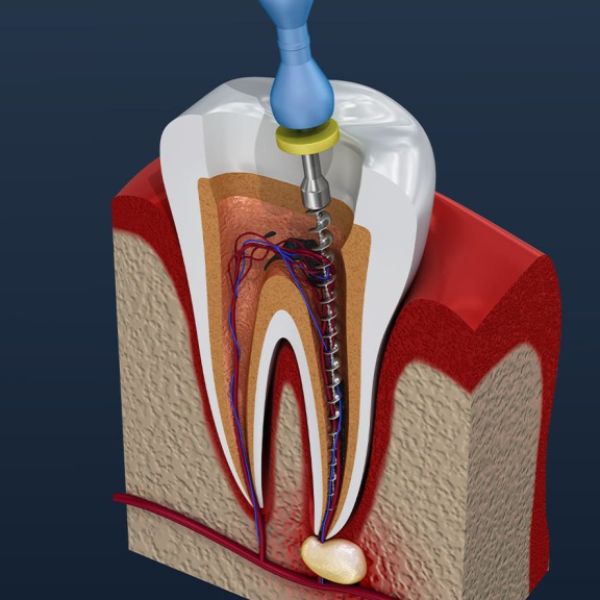

Trợ lý niềng răng

Tìm kiếm địa chỉ, bác sĩ niềng răng giàu kinh nghiệm.